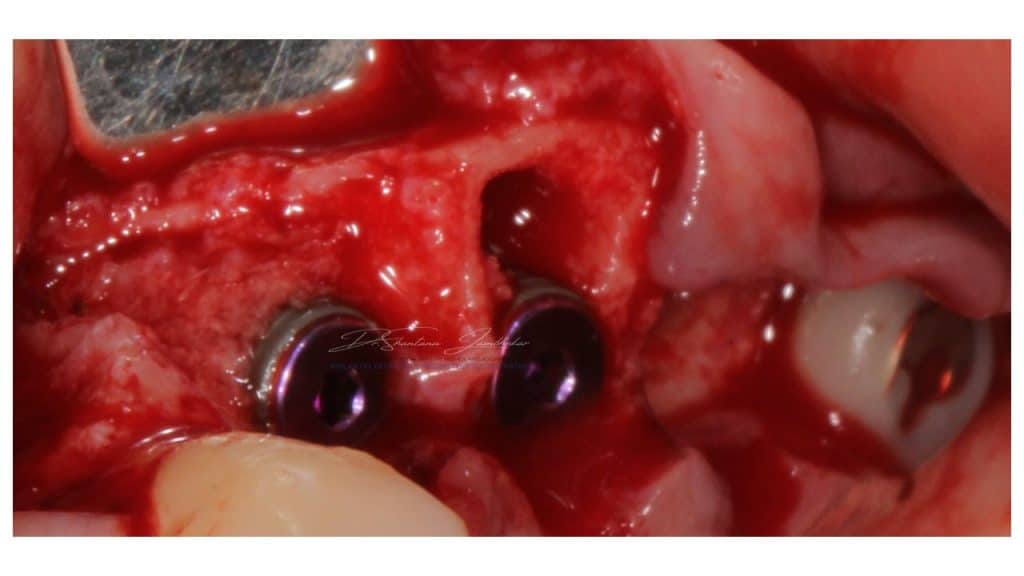

Immediate Implants (Type I) placed with site 23 & 24

Implants in situ with Mounts in Site 23,24 & 26

Covers screws connected with site 23,24 for closed healing & 26 with wide emergence custom healing abutment